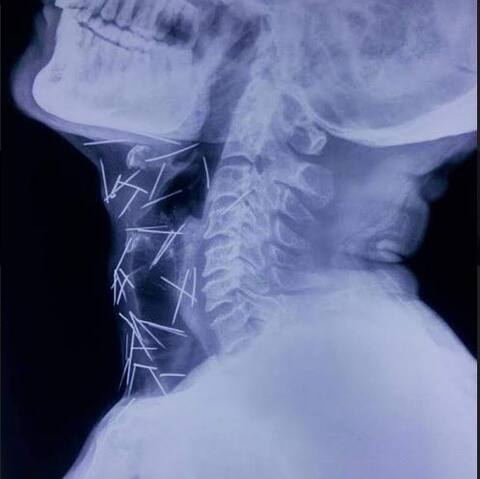

शरीरात 200 हून जास्त टाचण्या, मुंबईतील रुग्णावर उपचाराचं आव्हान

मुंबई : मुंबईतल्या रुग्णालयात उपचारासाठी दाखल झालेल्या एका रुग्णाला पाहून डॉक्टरही थक्क झाले आहेत. या व्यक्तीच्या शरीरात टाचण्यांचा साठा आढळला आहे. टाचण्यांची संख्या एक-दोन नव्हे, दहा-बाराही नव्हे, तर तब्बल 200 हून अधिक आहे. हा एक्स-रे ग्राफिक्सची कमाल नसून एका माणसाचा आहे. त्यामध्ये दिसणाऱ्या या बारीक रेघा म्हणजे आपल्या नेहमीच्या वापरातल्या टाचण्या आहेत. मुंबईतल्या जगजीवन राम रुग्णालयात आलेल्या या रुग्णावर उपचार करणं मुंबईतल्या डॉक्टरांपुढे एक मोठं आव्हान ठरलं आहे. कारण शेकडो पिना त्याच्या शरीरात घर करुन बसल्या आहेत. एखाद्या व्यक्तीच्या शरीरात शेकडो टाचण्या जाऊच कशा शकतात, हे एक मोठं कोडं आहे. या पिना आल्या कशा हे रुग्णाच्या कुटुंबीयांनाही ठाऊक नाही. एका मांत्रिकासोबत या रुग्णाचा संपर्क झाला होता. त्याच मांत्रिकानं एखाद्या खाद्यपदार्थात घालून या टाचण्या त्याच्या शरीरात घातल्याचा दावा केला जात आहे. 56 वर्षीय बद्रीलाल मीणा रेल्वेत पाणीपुरवठा कर्मचारी आहेत. मूळ राजस्थानच्या कोटा शहरात त्यांचं घर आहे. चार वर्षांपूर्वी त्यांना शुगरचा त्रास झाला. त्यानंतर पायावर हळूहळू जखमा व्हायला लागल्या. अचानक आलेल्या जखमांमुळे डॉक्टरही चक्रावले. त्यामुळे बद्रीलाल यांचा एक्स-रे काढण्यात आला. मात्र त्यानंतर जे समोर आलं ते धक्कादायक होतं. पायापासून घशापर्यंत, हातापासून पाठीपर्यंत बद्रीलाल यांच्या शरीरात शेकडो टाचण्या आहेत. घशात रुतून बसलेल्या पिनांमुळे त्यांना बोलणं आणि खाणंही जिकीरीचं झालं आहे. बद्रीलाल यांच्यावर उपचार कसा करावा, असा प्रश्न डॉक्टरांना पडला आहे. त्यासोबतच इतक्या पिना नेमक्या शरीरात गेल्याच कशा, या प्रश्नानंही डॉक्टरांसह अनेक जण हैराण झाले आहेत.